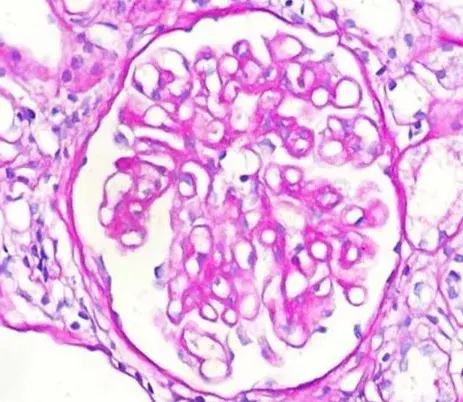

A biópsia renal revelou GN crescêntica necrotizante difusa sem hipercelularidade endocapilar. Alguns raros glomérulos continham células gigantes multinucleadas.

A avaliação da microscopia de luz pode ajudar na diferenciação de casos de **GN por anti-MBG** de casos **GN-ANCA**, já que na GN anti-MBG não observamos hipercelularidade endocapilar e pode ser identificado a presença de células gigantes multinucleadas, estas células gigantes multinucleadas resultam a natureza explosiva e a rápida destruição dos glomérulos observadas em anti-MBG

Desta forma, a presença de lesões crescentes temporalmente semelhantes e células gigantes multinucleadas na microscopia de luz (MO) pode ajudar no diagnóstico precoce.